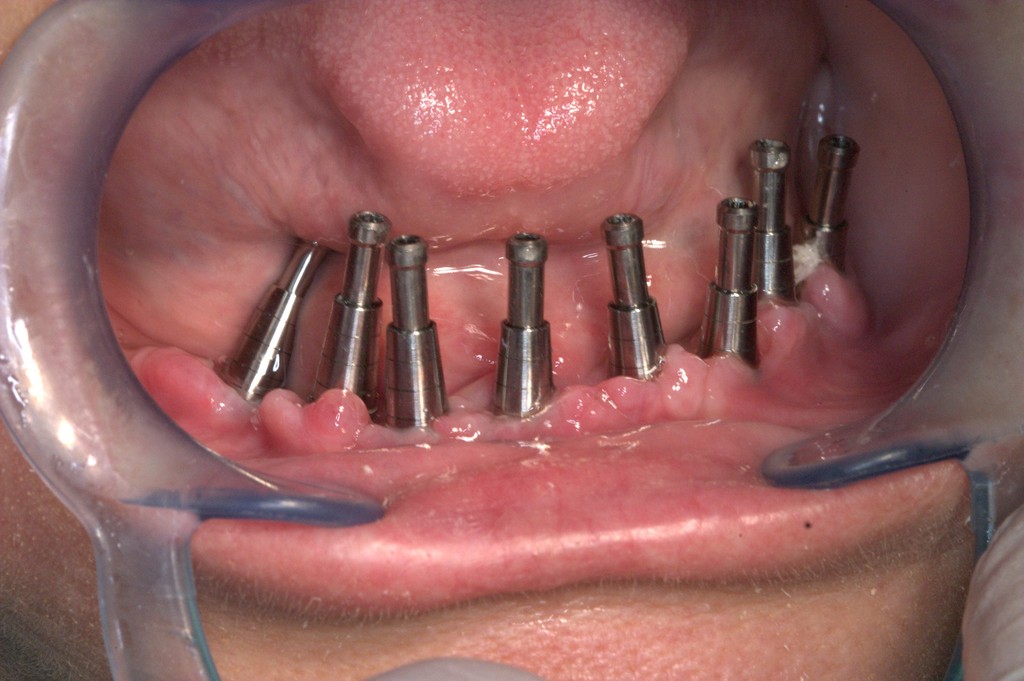

REHABILITACIÓN IMPLANTOSORTADA EN MANDÍBULA Y MAXILAR.